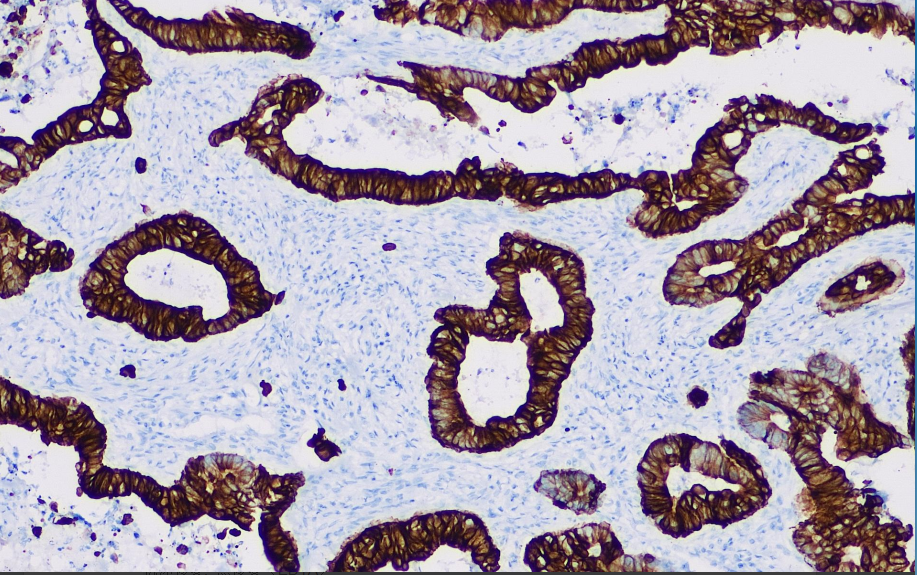

Cytokeratin 20 (46kD) is present in normal gastrointestinal epithelium, migratory epithelium, Merkel cells and tumors of their origin, whereas it is negatively expressed in breast, lung, ovarian non-mucinous and neuroendocrine tumors. This antibody is primarily used to label gastrointestinal epithelial cells and tumors of their origin.

CK20 antibody reagents can specifically bind to CK20 molecular antigens. Immunohistochemistry kits containing CK20 antibody reagents are suitable for the auxiliary diagnosis of gastrointestinal adenocarcinoma, cholangiocarcinoma, pancreatic cancer, transitional cell carcinoma, and ovarian mucinous tumors.